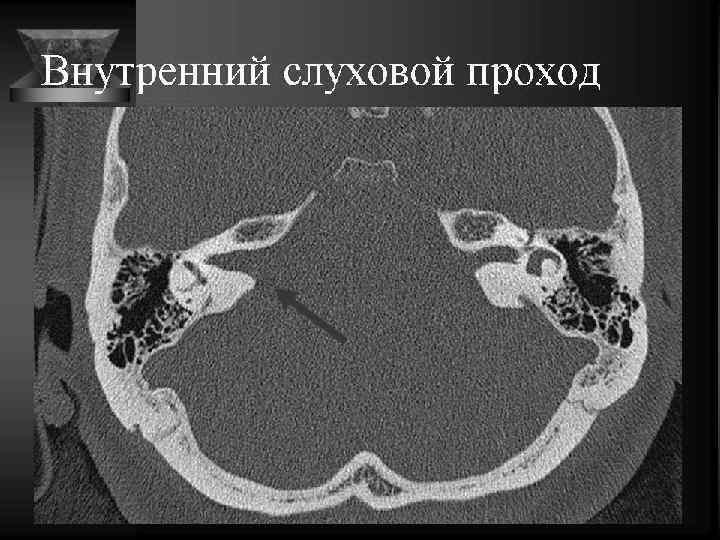

Внутреннее ухо и верхушка пирамиды • Улитка: деминерал-я костной капсулы, спирал-й канал улитки и его просвет, оссификация • Преддверие и полукружные каналы, интактные стенки, оссификация • Внутр. слух. проход: расширение, неровн-ть контура, деструкция кости, стеноз • Канал лицев. нерва до коленч. ганглия. • Водопровод преддв-я и водопр. улитки. • Верхушка пирамиды: губчатая или пневматизирована, наличие секрета, наличие образований